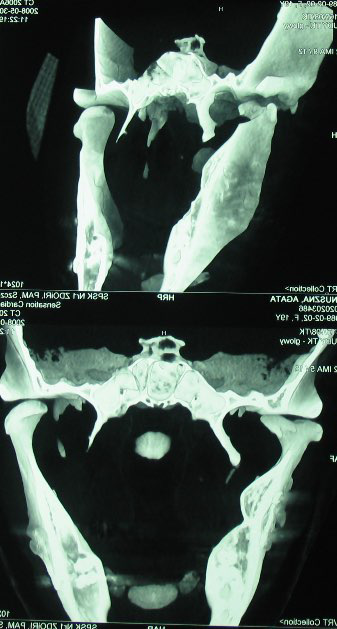

In patient XY, jaw opening improvement was taking place at the slowest rate. After 6 weeks of rehabilitation, 13 weeks post injury, jaw opening in the patient expanded from 10 to 27 mm. The late beginning of rehabilitation was associated with dislocation in TMJ, which primarily occurred due to a complex injury – a multi-fragmented fracture within the mental region, a bilateral fracture within the area of the mandible angles, a right-side fracture of the condyle process and the styloid process, with the knock-out of lower central incisors (Figure 2). The displacement of TMJ occurred for the 2nd and 3rd time in the patient, in whom the fragments of the mandible were stabilized through the use of ORIF, and finally permanent maxillomandibular fixation was applied after placing a partial mobile prosthesis in the oral cavity, which recreated lower central incisors. Anxiety about the renewal of the TMJ displacement probably retarded full commitment to rehabilitation.

The CT scan of the skull in 3D reconstruction performed after 52 weeks of rehabilitation showed the deformation of the right condylar process and the cup on the side (Figure 6). Changes in the shape of the condyle head arose during a year’s rehabilitation of the oral cavity functions. At that time, the head of the condyle grew together with the torn off fragment of the head of condyle; the broken off side plate of the pterygoid process was still visible as a free fragment.

The late exposure (CT with 3D reconstruction was performed 5 weeks after the injury) of the avulsion of the lateral pterygoid muscle with a fragment of the head of the condylar process and the lateral plate of the pterygoid process was not only a diagnostic issue for us. Questions regarding further treatment have only partially been answered in experimental research.27, 28 Both of the above-mentioned studies showed the lateral pterygoid muscle as an element which stimulates distractive osteogenesis after a condylar process fracture, and which along with the injured joint disk may be an important factor in the etiology of TMJ ankylosis.27, 28 In case of disruption of the muscle, the stimulation of osteogenesis will not take place.

In the case of our female patient XY, the late diagnosis of the avulsion of the lateral pterygoid muscle was the cause of the recurring dislocation of the condylar process. It was probable that the muscle avulsion and functional rehabilitation prevented TMJ from getting stiff.